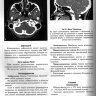

В первой главе учебного пособия изложена нормальная и лучевая анатомия шеи по данным рентгенологического исследования, УЗИ, КТ и МРТ с указанием анатомических структур на соответствующих рисунках. Вторая-десятая главы посвящены визуализации наиболее часто встречающихся неопухолевых и опухолевых заболеваний шеи, в которых представлены данные методов лучевой визуализации. Даются рекомендации по тактике лучевого исследования, приводится дифференциальная диагностика. Рассматриваются вопросы этиологии, патогенеза, морфологии и клинических проявлений заболеваний шеи. Описываемые нозологические формы иллюстрированы соответствующими изображениями. Для ординаторов, обучающихся по специальностям: 31.08.08 — Радиология, 31.08.09 — Рентгенология, 31.08.11 — Ультразвуковая диагностика; аспирантов 3.1.25 — Лучевая диагностика, а также врачей смежных специальностей, занимающихся обследованием и лечением пациентов с различными заболеваниями шеи. Учебное пособие может быть рекомендовано для подготовки в системе постдипломного непрерывного медицинского образования.

Примеры страниц из книги "Визуализация заболеваний шеи" - Труфанов Г. Е., Припорова Ю. Н.